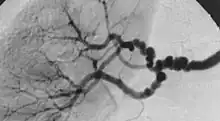

| The "string-of-beads" feature in multi-focal fibromuscular dysplasia. The sign is caused by areas of relative stenoses alternating with small aneurysms. | |

Multi-focal (previously known as medial) fibroplasia involves thickening of the media and collagen formation. It is typically reported as having the appearance of a "string of beads" on angiographic review.[4] "The 'bead' component is often larger than the normal arterial lumen, and in a subset of patients with FMD, aneurysms are present that may require treatment."[4] The multi-focal subtype of FMD accounts for nearly 80% to 90% of all FMD cases.[4]